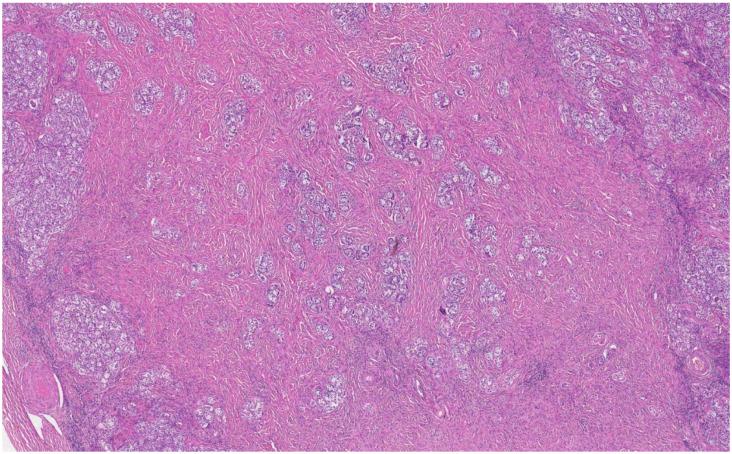

: We report the clinical case of female patient with 46,XY difference of sexual development (DSD) and discuss the challenges in the differential diagnosis between complete gonadal dysgenesis (also called Swyer syndrome) and complete androgen insensitivity syndrome. : The patient's with primary amenorrhea gynaecological examination and magnetic resonance imaging (MRI) revealed the absence of the uterus and a very short vagina. Two sclerotic structures, similar to ovaries, were recognised bilaterally in the iliac regions. Hormonal assay tests revealed hypergonadotropic hypogonadism and the testosterone level was above normal. The karyotype was 46,XY and a diagnosis of Swyer syndrome was made. At the age of 41, the patient underwent a gynaecological review and after evaluating her tests and medical history, the previous diagnosis was questioned. Therefore, a molecular analysis of sex-determining region Y (SRY) and androgen receptor (AR) genes was made and the results instead led to a definite diagnosis of complete androgen insensitivity syndrome. : The presented case illustrates that differentiating between complete gonadal dysgenesis and complete androgen insensitivity can be challenging. A well-established diagnosis is crucial because the risk of malignancy is different in those two syndromes, as well as the timing and importance of gonadectomy.

该患者因原发性闭经接受妇科检查和磁共振成像(MRI)检查,结果显示子宫缺失,阴道非常短。在髂区双侧发现两个类似于卵巢的硬化结构。激素测定试验显示促性腺激素性性腺功能减退,睾酮水平高于正常。核型为 46,XY,诊断为 Swyer 综合征。患者在 41 岁时接受妇科复查,在评估她的检查和病史后,对之前的诊断提出质疑。因此,进行了性决定区 Y(SRY)和雄激素受体(AR)基因的分子分析,结果明确诊断为完全雄激素不敏感综合征。